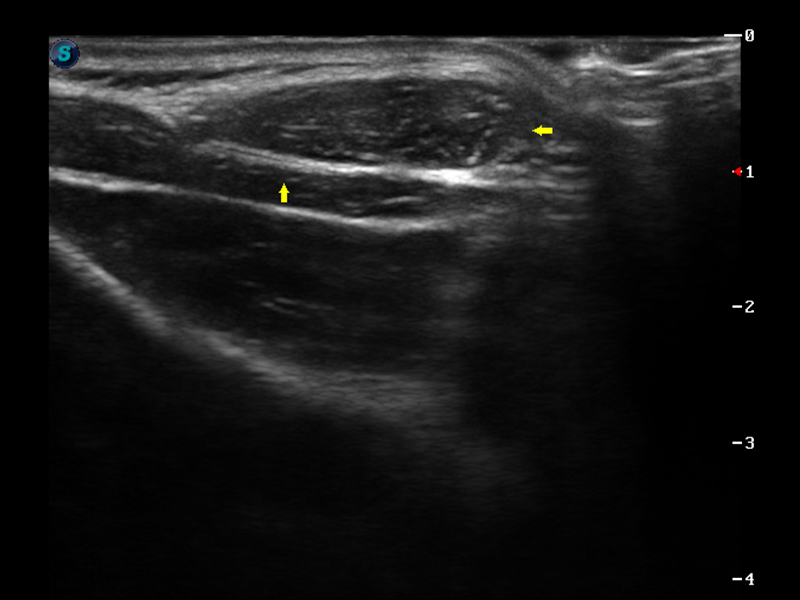

S9便携式彩色多普勒超声诊断仪是球速体育入口研发的高端便携彩超设备,外观设计新颖、产品性能卓越。S9在便携超声领域采用了突破传统的触摸屏交互设计,并以先进的软件硬件技术和设计理念,为您带来清晰的图像质量、稳定的工作性能和便捷的操作体验。